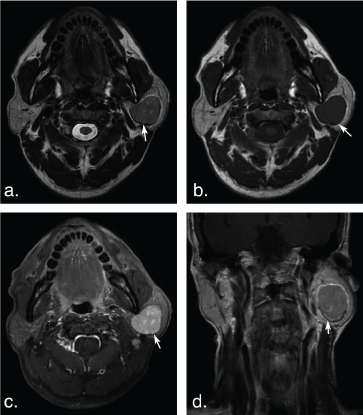

Figure 5: A 63-year-old man with Warthin tumors in the deep lobe of the left parotid gland. T2 weighted image (a) and T1 weighted image (b) show a well-defined, lobulated, heterogonous tumor. Lesion with irregular cystic area (arrowheads) and solid nodule (arrows). The solid portion of the tumor shows hypoinentse signal on T2 weighted and T1 weighted MR images, and mild enhancement (arrow) on axial contrast-enhanced fat-suppressed T1 weighted image (c) and coronal non-fat suppressed T1 weighted image (d) (arrows). View Figure 5

Figure 6: A 74-year-old man with multiple Warthin tumors in the superficial lobe of the right parotid gland and the deep lobe of the left parotid gland. Axial T2 weighted image (a) and axial T1 weighted image (b) show multiple, well-defined, ovoid tumors in bilateral parotid (arrows). The tumors show hypointense signal on T2 weighted and T1 weighted MR images, and mild enhancement (arrow) on axial contrast-enhanced fat-suppressed T1 weighted image (c) and coronal non-fat suppressed T1 weighted image (d) (arrows). View Figure 6